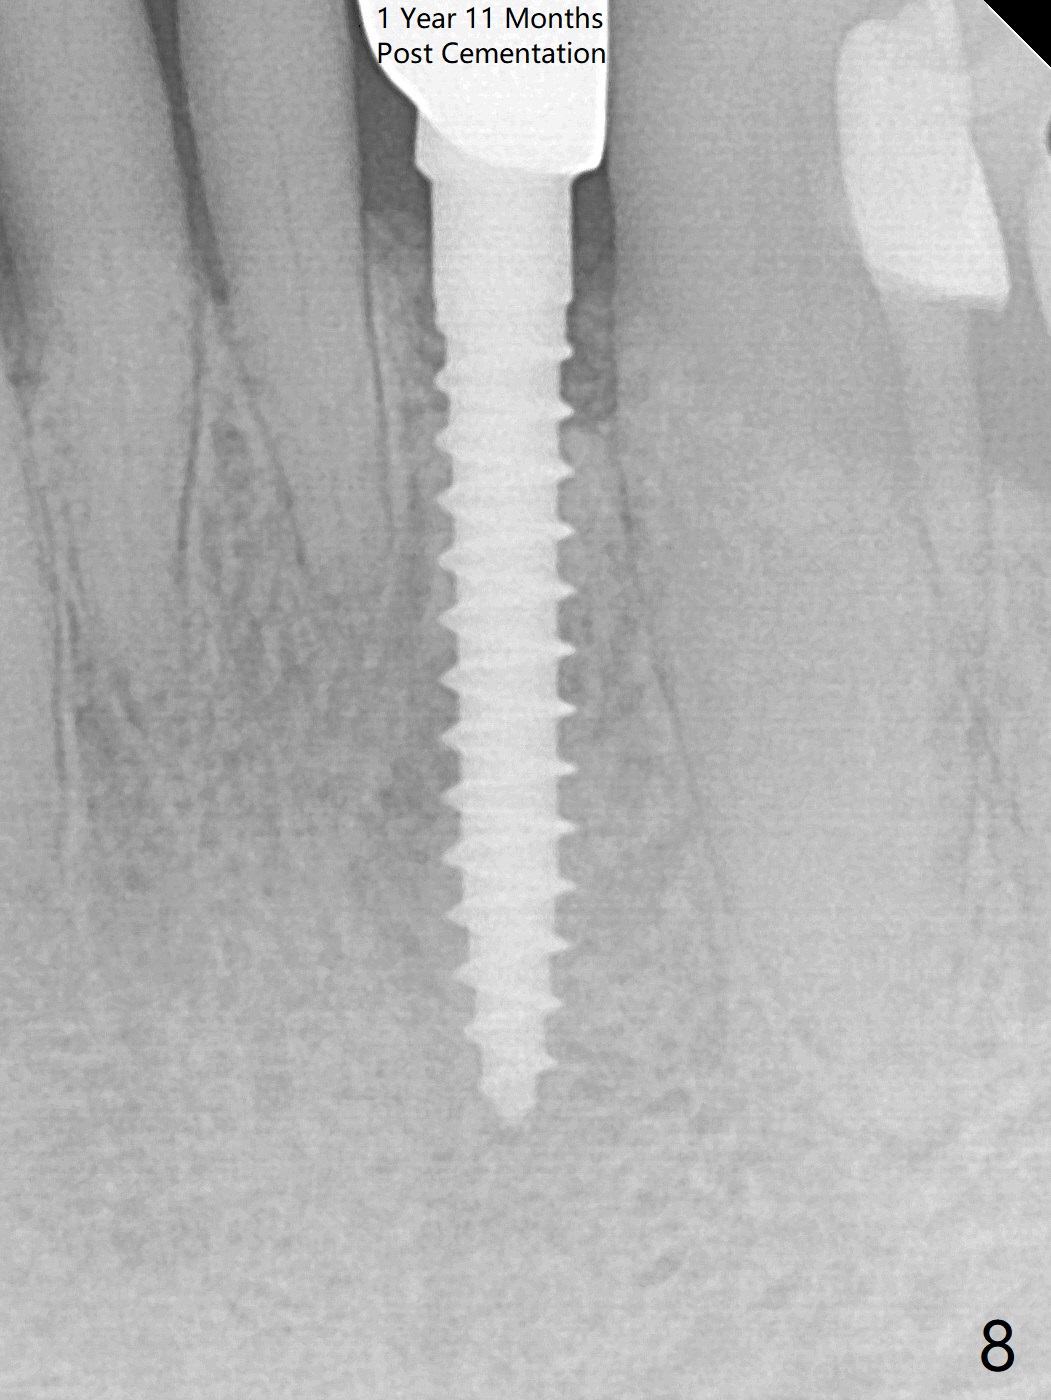

The tooth #23 is going to be extracted because the patient cannot masticate normally with mobility (Fit.1). The gingival depth is measured 2-4 mm after extraction. The 1st intraop PA taken with 1.2 mm drill for 16 mm shows the mesiodistal width is 5.11 mm (Fig.2); a 2.5x14(2) mm 1-piece implant is placed with >35 Ncm (Fig.3 with allograft placed). Following abutment preparation, an immediate provisional is fabricated to close the socket (Fig.4 P). There is no bone loss (Fig.5) or gingival inflammation (Fig.6 after reprep) 3 months postop. The narrow implant (2.5 or 2.0 mm) is indicated in the narrow edentulous space. The distal crest seems to be reduced in density and lower in height 1 year 7 months (Fig.7) and 1 year 11 months (Fig.8) post cementation. The severity does not worsen probably related to use of water pik. The crown looks bulky probably due to too large the abutment and too buccal placement of the implant (Fig.9, 10, as compared to Fig.1). A 2 mm implant may help?